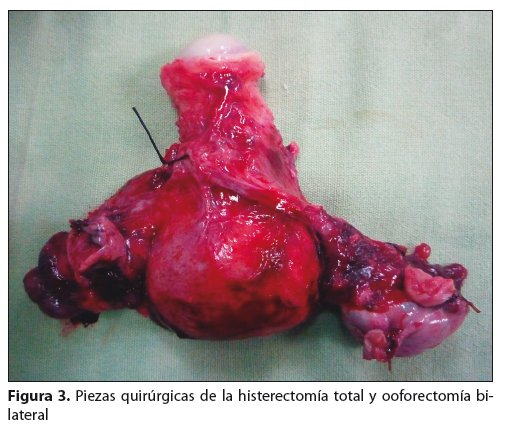

Se realiza laparotomía diagnóstica, etapificadora y citoreductora: histerectomía abdominal total, ooforectomía bilateral, (fig. 2) omentectomía, apendicectomía, biopsia de correderas parietocólicas derecha e izquierda, cepillado de cúpula diafragmática, citología de líquido ascítico.

Se envía durante el trans quirúrgico una muestra de la masa para biopsia por congelación, la cual reporta cistoadenocarcinoma seroso papilar de ovario, con etapificación quirúrgica IIIc. Posterior a la cirugía la paciente pasa a salas generales para su recuperación donde se confirma el diagnóstico histopatológico. La paciente cursa su post quirúrgico en forma favorable, por lo que se le indica su alta hospitalaria al tercer día, para continuar su tratamiento con quimioterapia en el servicio de oncología del Hospital Clínico Viedma.

Estadio I. Tumor limitado a los ovarios, estadio II cuando el tumor se extiende a la pelvis, estadio III cuando afecta uno o ambos ovarios con implantes fuera de la pelvis y/o ganglios retroperitoneales o inguinales positivos, con extensión histológica a intestino delgado o epiplón y estadio IV con metástasis a distancia2. Correspondiendo el caso presentado al estadio IIIc por la presencia de actividad tumoral dependiente de ambos ovarios con múltiples implantes mayores de 2 cm en fondo de saco, ambas correderas parietocólicas y epiplón.